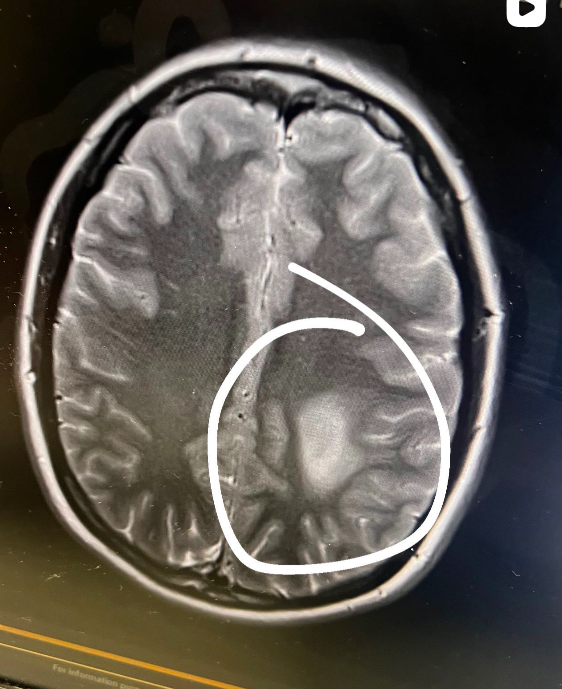

Az új-zélandi Paige Suisted-t mélyen megdöbbentette, amikor tavaly áprilisban gyógyíthatatlan agydaganatot diagnosztizáltak nála. A körülbelül golflabda méretű elváltozás egy különösen kritikus területen helyezkedett el, és nyomást gyakorolt a teste jobb oldalát irányító idegekre. Mivel a műtét túl kockázatos lett volna, a fiatal nő intenzív kemoterápiás és sugárterápiába kezdett. Paige, aki korábban modellként és ékszerárusítóként dolgozott, elkezdte dokumentálni nehéz mindennapjait a közösségi médiában.

Fotó: Instagram/journey_through_cancer